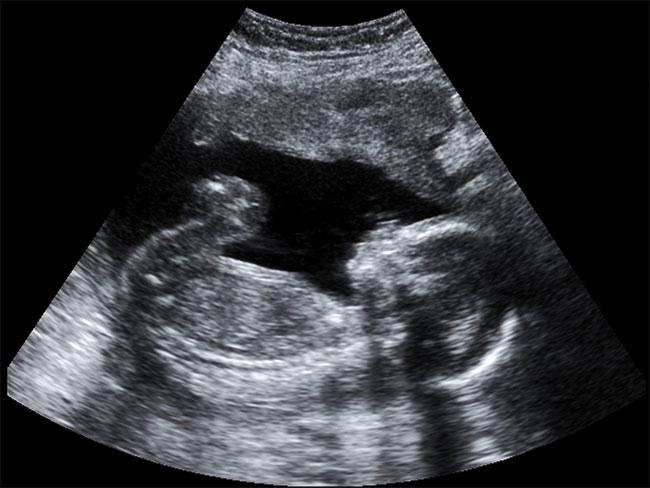

การดิ้นของทารกในครรภ์ บอกอะไรเราหลายอย่าง ที่แน่ๆ ก็เป็นสัญญาณหนึ่งที่บ่งบอกว่าลูกยังมีชีวิตอยู่ การดิ้นของทารกในแต่และช่วงเวลา และช่วงอายุครรภ์ อาจแสดงให้เห็นในแบบต่างๆ กัน เช่น ในช่วงไตรมาสแรก คุณแม่แทบไม่ทราบเลยว่าลูกมีการดิ้นเกิดขึ้นแล้ว โดยเด็กจะเริ่มดิ้นตั้งแต่อายุครรภ์ประมาณ 6 - 7 สัปดาห์ จะเห็นก็จากตอนที่คุณหมอทำการตรวจอัลตราซาวด์ให้ดู เด็กจะมีการเคลื่อนไหวของแขนขา กระโดดเด้งตัว ลอยไปลอยมาในถุงน้ำคร่ำ เนื่องจากลูกยังเล็กมาก จึงไม่ทำให้เกิดความรู้สึกรับรู้ในท้องแม่ เนื่องจากการที่แม่ท้องจะรับรู้การดิ้นของลูกได้ ต้องมีอวัยวะส่วนหนึ่งส่วนใด ของทารกสัมผัสโดยตรงกับผนังมดลูกแม่ ซึ่งต้องมีความแรงพอสมควร ที่ทำให้แม่รับรู้ได้ ดังนั้นในช่วงเล็กๆ เด็กทารกตัวเล็ก จึงไม่ได้ดิ้นแรงพอให้แม่รู้สึกได้ ต้องรอให้ทารกขนาดใหญ่ขึ้น จนมีแรงดิ้นแรงพอให้แม่รู้สึกได้ การดิ้นบางครั้งเป็นการตอบสนองต่อสิ่งเร้าจากภายนอกที่มากระตุ้น เช่น เสียงเพลง แสง หรือการสัมผัสที่ท้องของพ่อและแม่ จะเห็นว่าลูกมีการตอบสนองต่อสิ่งเหล่านี้ได้ เมื่ออวัยวะรับสัมผัสเหล่านี้เริ่มพัฒนา ซึ่งถือว่าเป็นสัญญาณที่ดีที่ลูกจะได้เรียนรู้ และตอบสนองต่อสิ่งต่างๆ ที่มากระตุ้น เพื่อสร้างให้เกิดพัฒนาการของทารกตั้งแต่อยู่ในครรภ์

ในท้องแรกที่แม่ยังไม่มีประสบการณ์การตั้งครรภ์มาก่อน ดังนั้นการรับความรู้สึกว่าลูกดิ้น ในครรภ์แรก (ท้องแรก) จะตกประมาณอายุครรภ์ 18 - 20 สัปดาห์ ส่วนในท้องหลังที่แม่มีประสบการณ์ตั้งครรภ์มาแล้ว จะรับรู้ความรู้สึกลูกดิ้นได้เร็วขึ้น 2 - 4 สัปดาห์ คือประมาณ 16 - 18 สัปดาห์ ทั้งนี้ขึ้นอยู่กับปัจจัยอื่นๆที่อาจมีอิทธิพลต่อการรับรู้การดิ้นของทารกในครรภ์ เช่น ปริมาณน้ำคร่ำ ถ้าน้ำคร่ำปริมาณมาก ผนังหน้าท้องจะตึง โอกาสที่ส่วนของทารกสัมผัสกับผนังมดลูก ก็น้อยกว่าในภาวะน้ำคร่ำที่น้อย โอกาสรับรู้การดิ้นก็น้อยลง ความหนาของผนังหน้าท้องแม่ ในแม่ที่หน้าท้องหนา (ท้วมหรืออ้วน) ก็รู้สึกรับรู้การดิ้นน้อยกว่าแม่ที่ผนังหน้าท้องบาง รวมถึงตำแหน่งการเกาะของรก ถ้ารกเกาะขวางทางด้านหน้า เสมือนเพิ่มความหนาของผนังหน้าท้อง การรับรู้การดิ้นก็น้อยลง นอกจากนี้ท่าทางของลูกในท้อง รวมถึงขนาดและจำนวนของทารกในครรภ์ ก็มีผลต่อการรับรู้ของแม่ต่อการดิ้นของลูกในท้อง นอกจากนี้การที่แม่เคยไปรับการตรวจอัลตราซาวด์ดูทารกในครรภ์มาก่อน การได้เห็นทารกที่กำลังดิ้นขณะตรวจ ก็จะทำให้แม่เห็นภาพและเข้าใจรับรู้ถึงการดิ้นของลูกได้เร็วขึ้นเช่นกัน